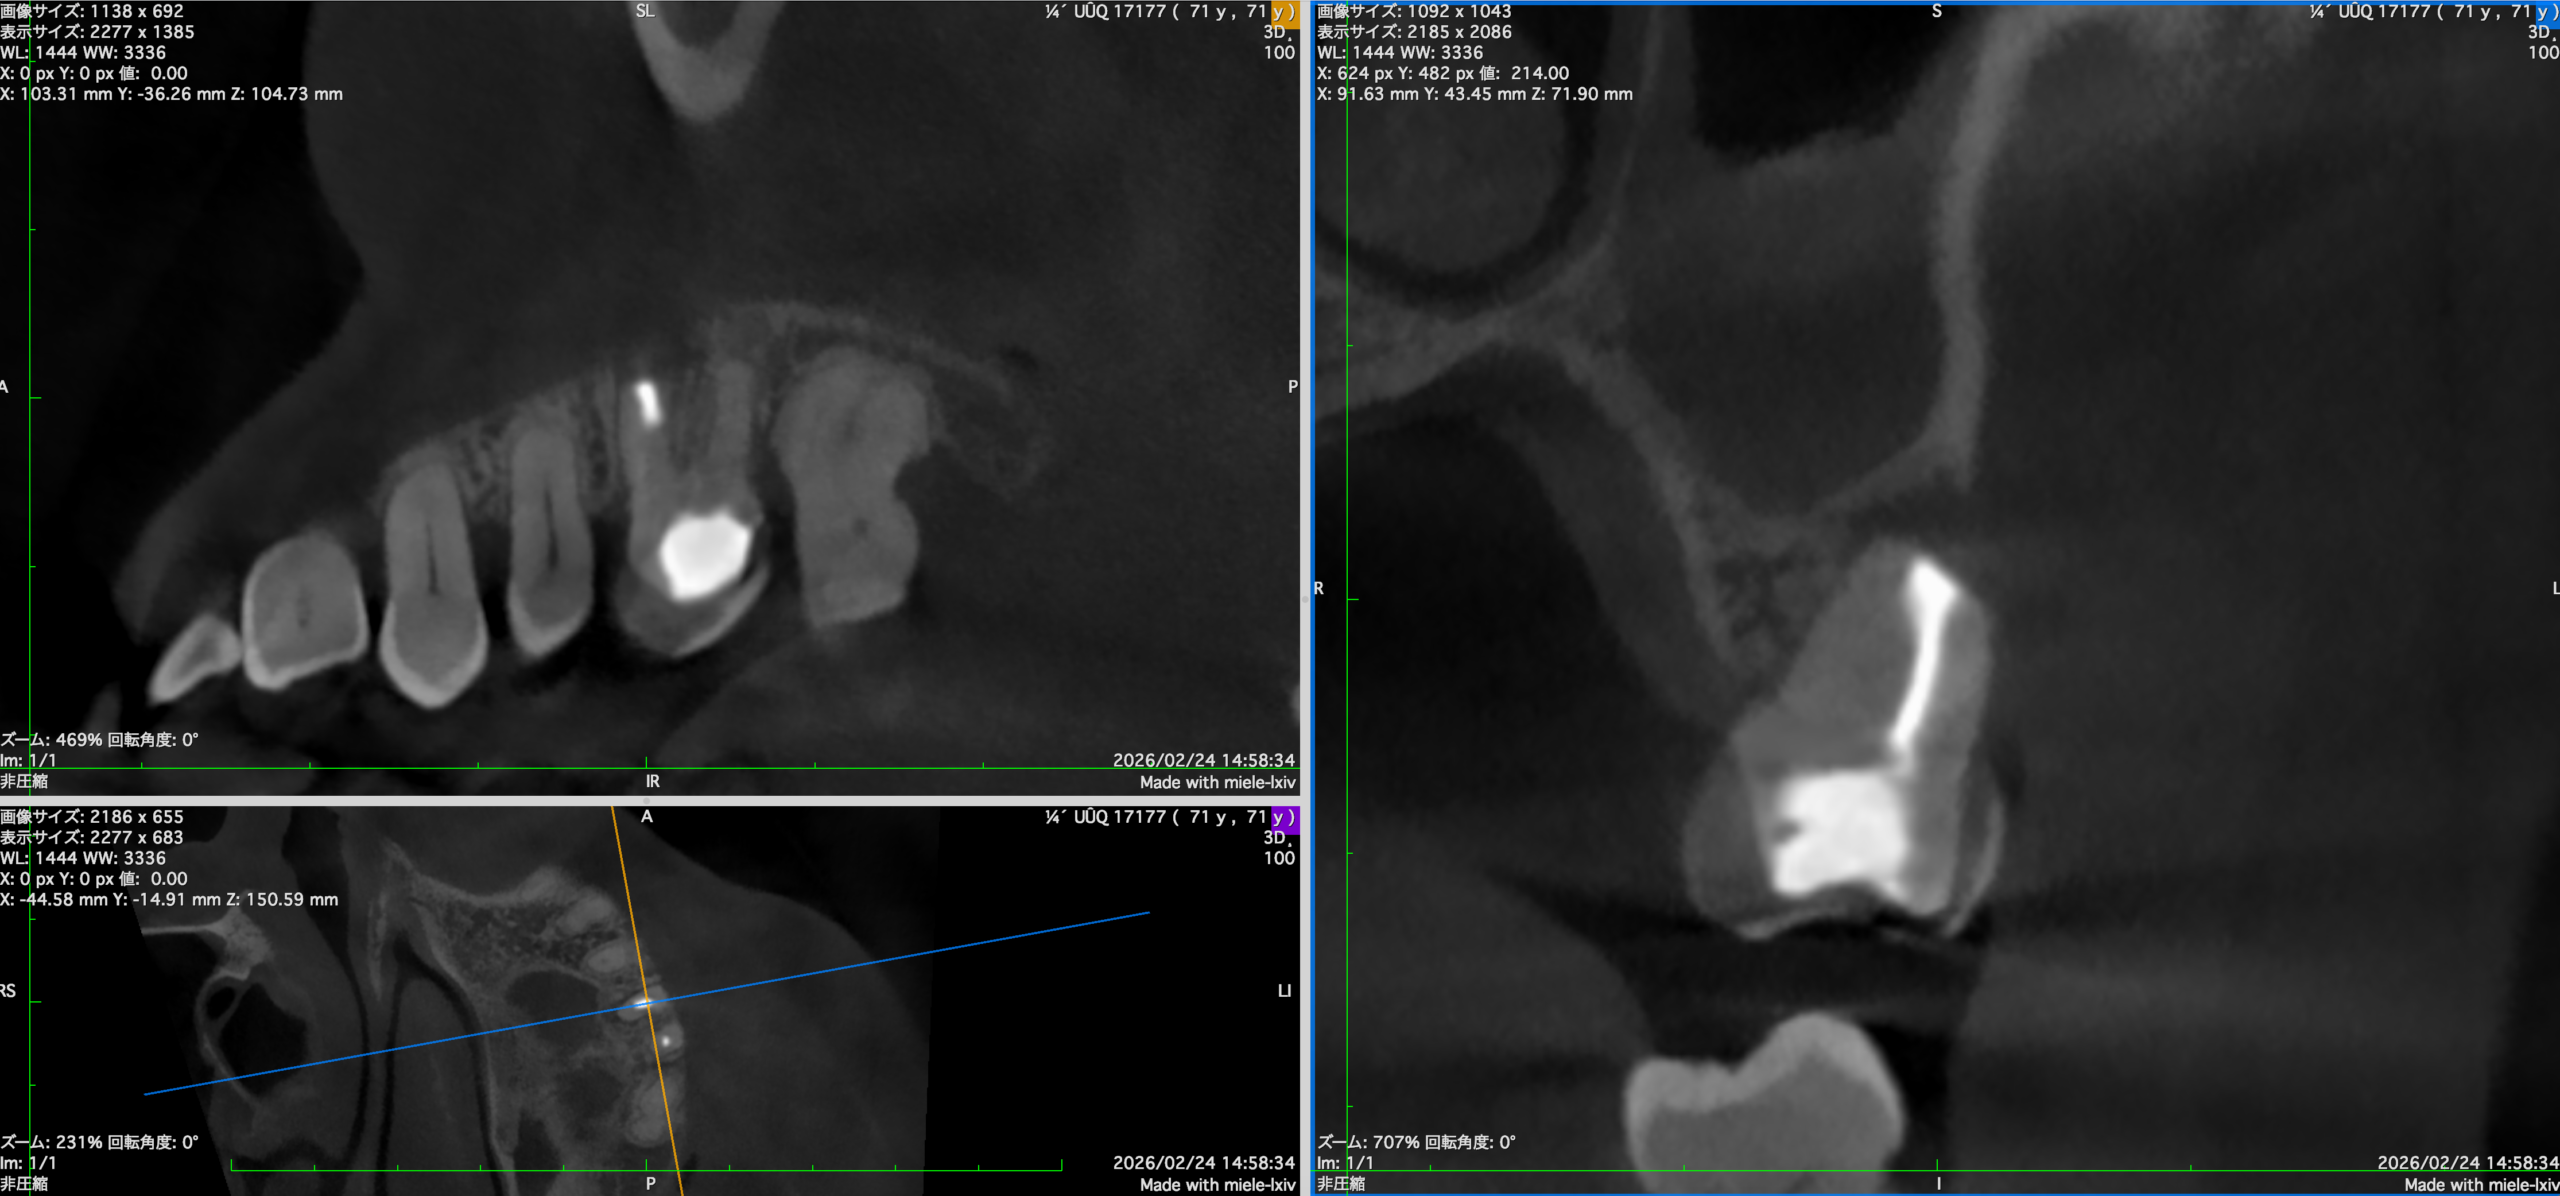

#14 MB+DB Apicoectomy 6M recall(2026.2.27)

Sinus tractと圧痛は消失したようだ。

画像判断は以下である。

MB

DB

P

半年前の術後と比較した。

術後の骨欠損は大きく回復している。

が、まだ道半ばだ。

ということでかかりつけ医の先生には最終補綴の装着を依頼した。

次回はもう半年後の1yr recallである。